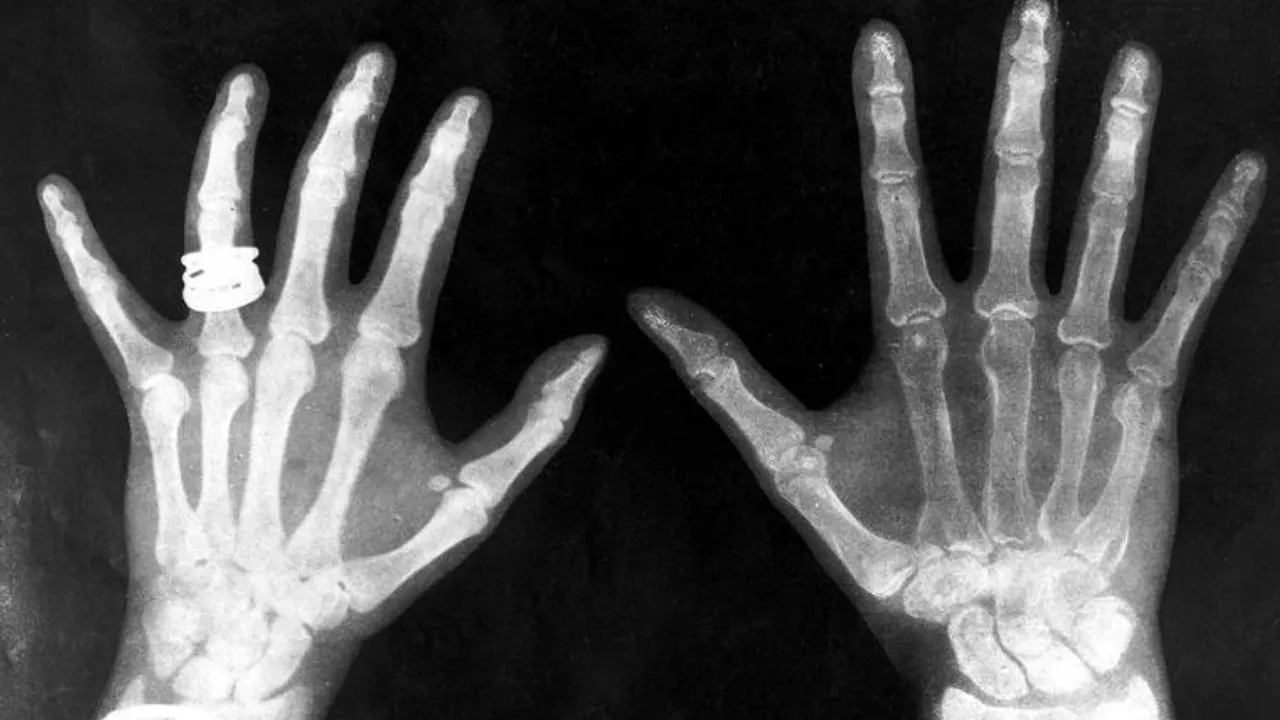

Yeni geliştirilen bu çip X-ray gibi çalışabiliyor. X-ray'in oldukça zararlı olan ışınlarının aksine 200 GHz (gigahertz) ila 400 GHz arasındaki sinyaller kullanılıyor. Bu sayede X-ray özelliği taşısa da zararlarına sahih olmuyor.

İlerleyen yıllarda bu çiplere sahip akıllı telefonlar zarfların ve paketlerin içini rahatlıkla görebilecek. Bu tür cihazlar hastaneler tarafından hastaların sıvı alımı seviyelerini kontrol etmek için bile kullanılabilir.